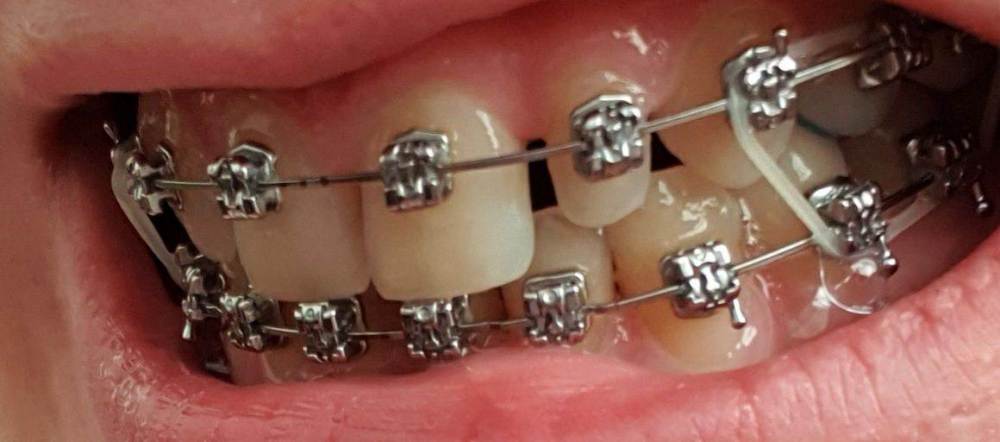

НадеждаВ Опубликовано 3 августа, 2022 Поделиться Опубликовано 3 августа, 2022 (изменено) Добрый день. Имеются 2 шипообразных резца. В стоматологии, где прохожу ортодонтическое лечение убеждают, что просто нарастить только их винирами не выйдет, т.к очень большие расстояния и если закрыть их, то боковые резцы по ширине будут неестественно широкими по отношению к центральным. Уменьшить промежутки тоже не видят возможности, т.к. сейчас передние зубы находятся между двумя нижними, при движении будут друг над другом. Поэтому предлагают установить 6 виниров от клыка до клыка, чтобы закрыть все промежутки и соблюсти соотношение ширины зубов. Действительно ли в моем случае это необходимо и нет реальной возможности ограничиться только двумя реставрациями с сохранением эстетики? Страшно пилить здоровые достаточно эстетичные зубы, особенно центральные резцы. На фото так же макет пластиковый, как мне предлагают сделать. Действительно ли боковые резцы должны быть несколько наклонены к центральным, а не быть абсолютно прямыми и зениты могут быть не четко по центру от зуба, а несколько в сторону уходить? 2. Вопрос касаемо самих виниров. Я хотела бы отбелить свои зубы на сколько получится и чтобы виниры были неотличимы от родных зубов. Я читала, что емах выглядят серовато, подходит ли в моем случае этот способ или лучше виниры, которые делают на рефракторе? Они, как я поняла, выглядят естественнее и тоньше, поэтому и обточки требуют меньше. ( один из Резцов на столько мал, что на него вроде только коронку можно установить). 3. Как оценить опытность врача? У ортопеда опыт всего 4 года, вдруг спилит слишком много. Так же смущает их техник, т.к у него скорее всего тоже небольшой опыт, сможет ли он сделать действительно эстетичную реставрацию? Когда делали макет и меня спрашивали про форму, я сказала, чтобы она максимально была похожа на мою и на макете боковые резцы сделали скошенные, как мои сейчас, но стёсанные, ведь это не эстетично и техник должен был это понимать. Изменено 3 августа, 2022 пользователем НадеждаВ Ссылка на комментарий

chervoncevdaniil Опубликовано 3 августа, 2022 Поделиться Опубликовано 3 августа, 2022 (изменено) Вам делали восковое моделирование и примерку для 6 винировв судя по фото,оплатите и закажите воскове моделироввание с примеркой только на 2 винира и оцените результат. Если вас устроит,то почему делайте,если нет,то обсуждайте другие ваарианты с большим количеством зубов. Исходя из фото номер 2 с моделировкой,все выглядит очень гармонично в случае 6 виниров Изменено 3 августа, 2022 пользователем chervoncevdaniil 1 Ссылка на комментарий

НадеждаВ Опубликовано 4 августа, 2022 Автор Поделиться Опубликовано 4 августа, 2022 @chervoncevdaniil спасибо. Да, макет на 6 зубов. Согласна, что выглядит органично, но я переживаю за зубы, ведь они здоровые, нормальные, а если раз их спилить, то все (это не касается боковых Резцов) я переживаю за целесообразность портить эмаль только ради двух миллиметров винира. По поводу макета на два зуба наверно хорошая идея, только когда мне ставили обратно брекеты, то положение зубов немного поменялось, щель между центральными зубами ушла почти ( хотя изначально у меня вообще ее не было), я правильно понимаю, что по идее, если хоть что-то сдвинулось, то по идее нужно вообще опять гипсовую модель переделывать? ещё сканировали челюсть на 3д, но почему-то этот снимок вообще не использовали. Ссылка на комментарий